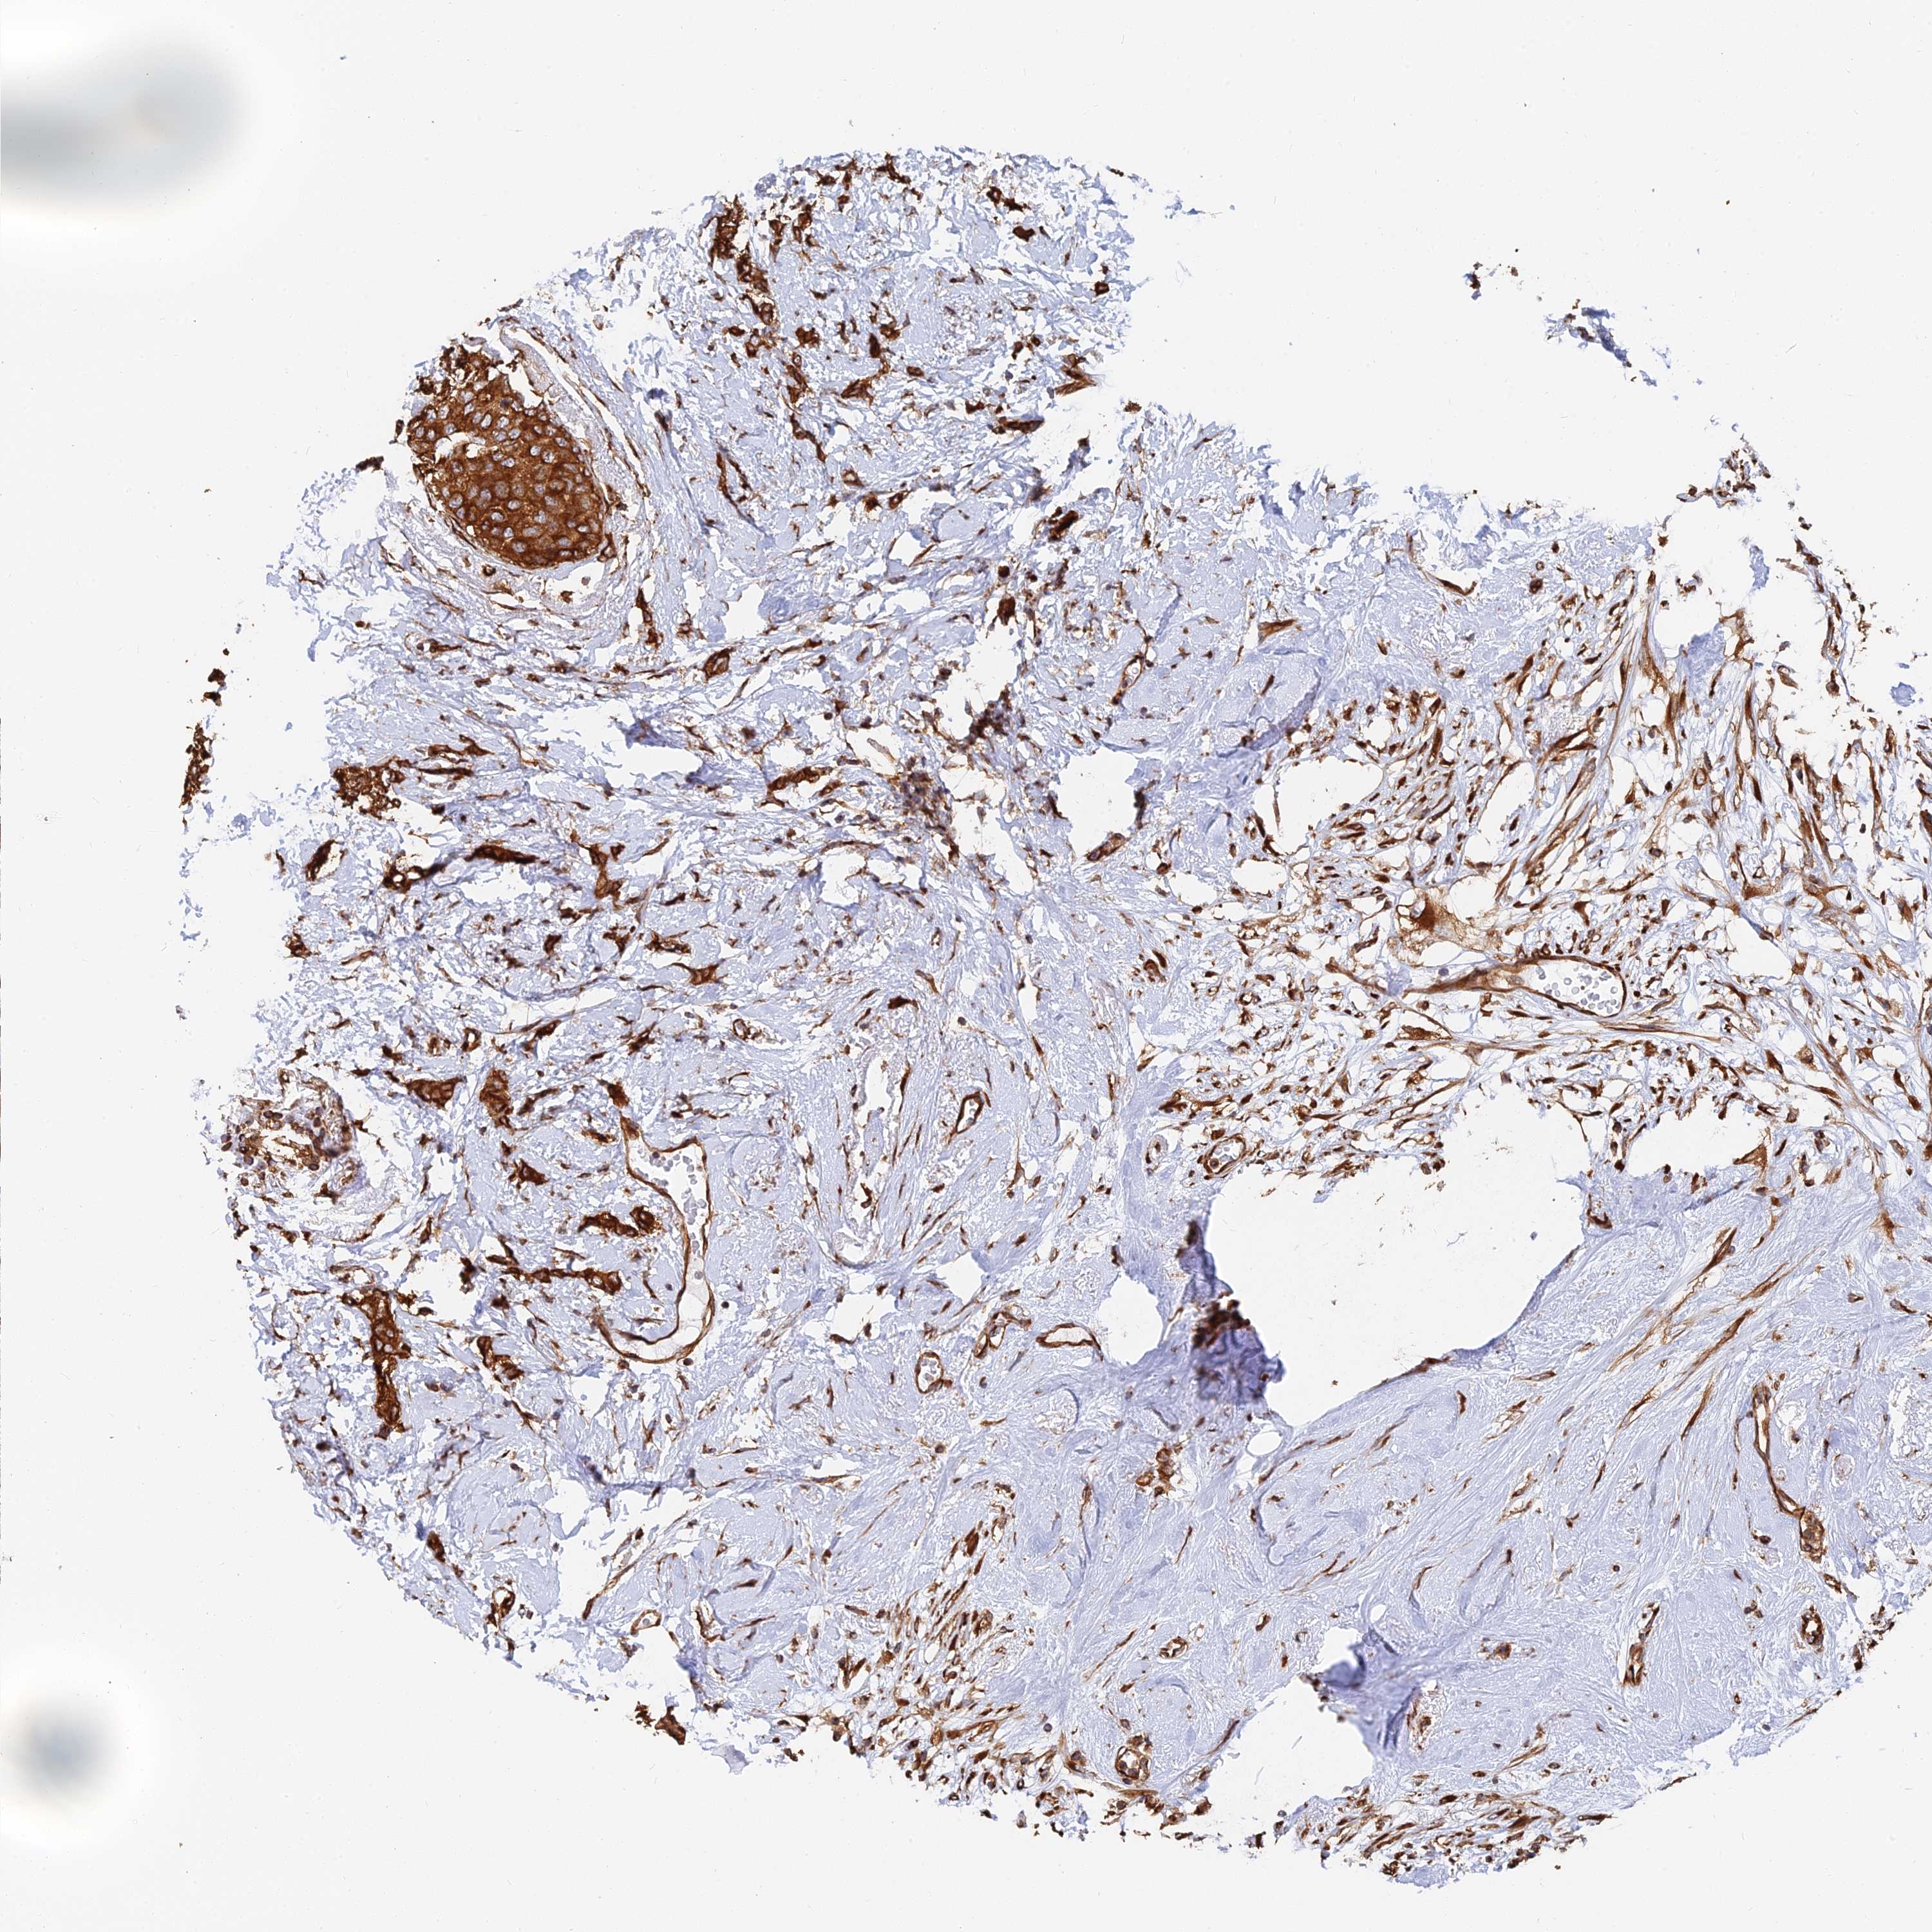

CANCER BREAST CANCER Show tissue menu

BRCA TCGA BRCA VALIDATION PROTEIN EXPRESSION

Breast cancer

Human cancer